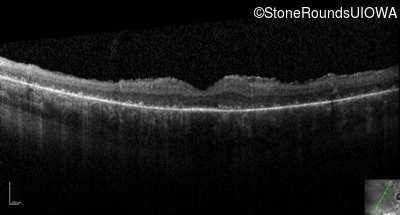

Optical Coherence Tomography - Right - 5/180 sc

Exemplar / OCT Stack